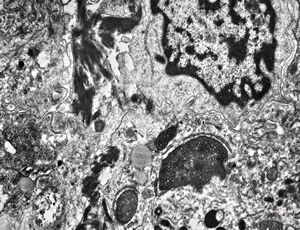

phagocytosed Nocardia (Actinomycetales) … cerebellar absces